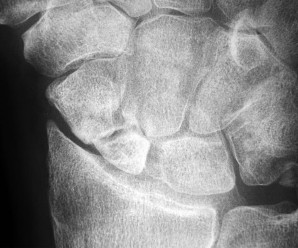

- الأشعة السينية (X-rays): هي الخطوة الأولى في تقييم الكسور، الخلوع، وتغيرات التهاب المفاصل. تساعد في تحديد مدى تدهور العظام والمسافات المفصلية. على سبيل المثال، تُظهر صور الأشعة السينية كسور السلاميات

أو كسور قاعدة العظم المشطي الخامس

، بالإضافة إلى علامات مثل "الدمعة الشعاعية" (Radiographic Teardrop) في الرسغ التي تمثل الزاوية الزندية الراحية الحرجة للكعبرة البعيدة

. - الأشعة المقطعية (CT Scan): توفر صوراً تفصيلية ثلاثية الأبعاد للعظام، وهي مفيدة جداً لتقييم الكسور المعقدة، مثل كسور العظم الخطافي (Hamate Hook Fracture) التي قد لا تظهر في الأشعة السينية العادية